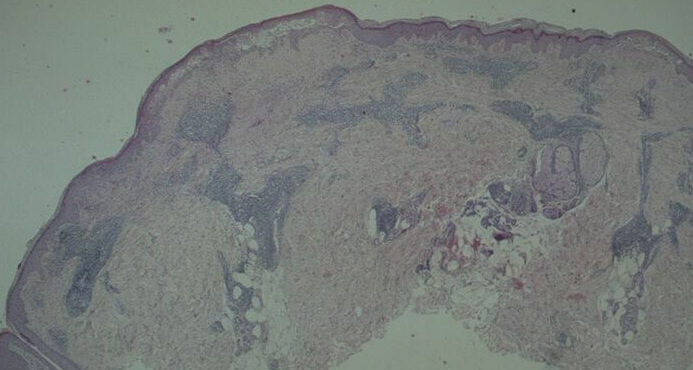

Read MoreHypertrophic lichen planus = الحزاز المنبسط الضخامي